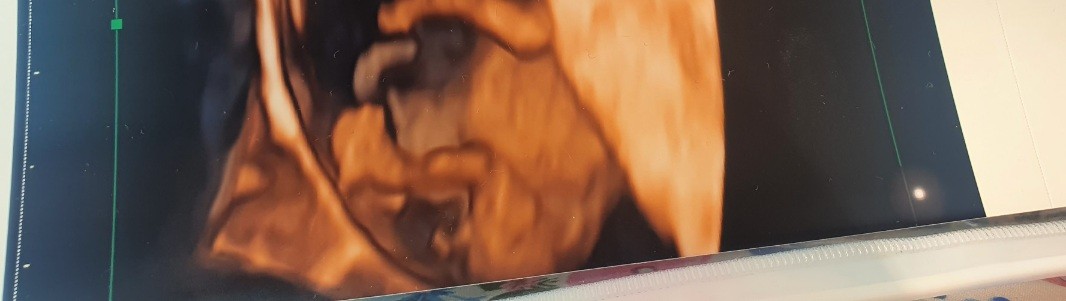

Doswiadczone mamusie. Czy na podstawie tych zdjęć da ocenic się płeć dziecka? Zaznaczam że to jest wczesna ciaza. 10 tydzień , ale czy przypadkiem nie da się po tych zdjęciach zauważyć plci dziecka?

Serio poczytaj. W 10 tyg płód ma jeszcze nie wykształcone zewnętrzne narządy rodne. Krótko mówiąc, to nie penis bo jeszcze go nie ma. Także żadne "być może".Być może;D

Serio poczytaj. W 10 tyg płód ma jeszcze nie wykształcone zewnętrzne narządy rodne. Krótko mówiąc, to nie penis bo jeszcze go nie ma. Także żadne "być może".